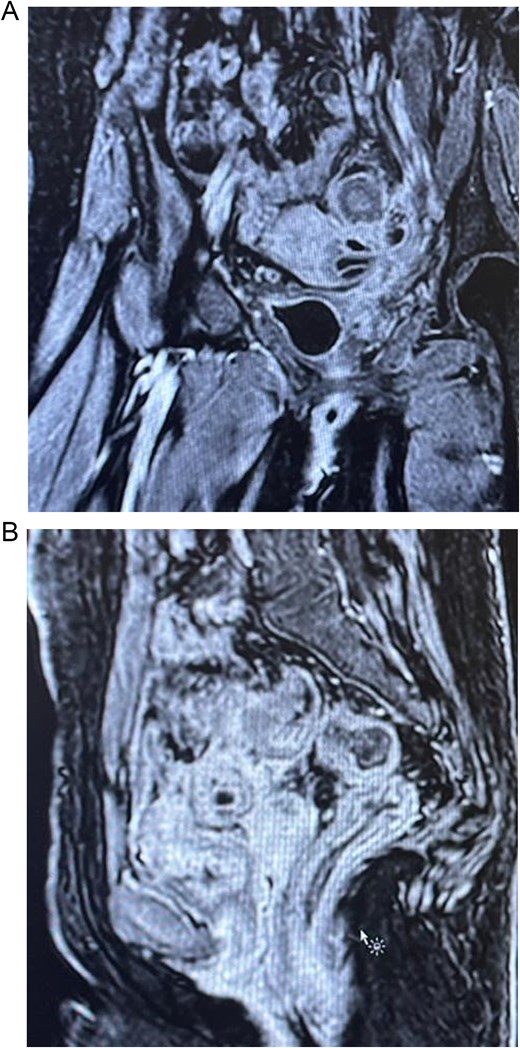

A sigmoidectomy was done, followed by an end to side colorectal anastomosis, with no intraoperative complications. The patient showed significant improvement in her symptoms after surgery by resolving her abdominal pain and urinary symptoms. Follow-up CT cystogram was done, which was unremarkable with no clear vesicorectal or vesicovaginal fistula (Fig. 4). Histopathology was performed and confirmed the presence of diverticular disease with chronic mucosal changes and fibrous tissue consistent with fistula formation, in addition to, the absence of histological evidence of dysplasia, or malignancy.

Showing axial section of the abdominopelvic CT scan with cystogram showing contrast filled urinary bladder with no clear vesicorectal or vesicovaginal fistula.